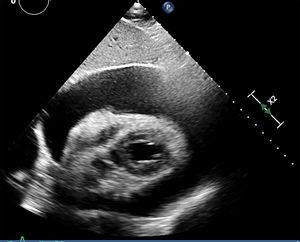

Cholesterol-induced pericarditis is a rare entity. We hereby present the case of an 81-year-old male admitted to our ICU due to severe pericardial effusion with early signs of hemodynamic compromise (Fig. 1). Diagnostic and therapeutic pericardiocentesis was performed that improved the patient's symptoms and his hemodynamic parameters. Around 1500mL of a yellowish fluid were obtained (Fig. 2). Cholesterol crystals, lipid micelles, and inflammatory cells were observed under the optic microscope (Fig. 3). The concentration of cholesterol in the pericardial fluid was higher compared to the patient's blood. Tuberculosis disease and hypothyroidism, rheumatoid arthritis and other systemic infections and autoimmune diseases were all ruled out. Cholesterol crystal are characteristic here and they are indicative of the chronicity of effusion and persistent inflammation of the pericardium. The concentration of cholesterol is usually the same or higher compared to blood. Treatment depends on the underlying disease. In the presence of hemodynamic compromise, we should always perform pericardiocentesis. In most cases, there will be relapses and pericardiectomy will be required.